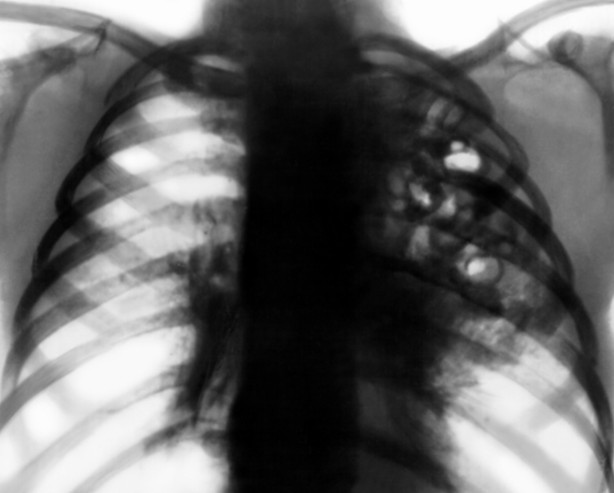

В изображении: рентгеновский снимок атипичной пневмонии с разрушением тканей.

На рентгенограмме можно обнаружить гипераэрацию и диффузные двухсторонние изменения. В начальной стадии изменения создают мутности фона, а затем инфильтрат становится плотнее, на его фоне видны просветления (воздушная бронхограмма).

Легионеллезная атипичная пневмония также характеризуется выслушиванием влажных хрипов в легких, но отличительной особенностью является выявление в ходе проведения рентгенологического исследования округлых инфильтратов, которые нередко располагаются в нескольких долях и способны сливаться между собой. Также возможно развитие плеврита с формированием плеврального выпота.